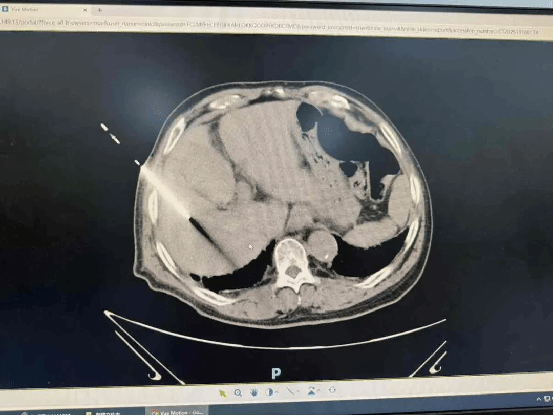

沈某某,2023年诊断小肠间质瘤,行手术后一直口服伊马替尼治疗,今年3月发现肝转移灶,行手术治疗半月前复查发现肝转移灶复发,患者就诊于我科决定行微波消融术,在我科客座教授(陕西省肿瘤医院)余国政专家指导下,于近日行微波消融术,消灭“肿瘤君”,过程顺利,短短几分钟,无痛苦解决新烦恼。

73岁的魏大爷,3月来体重明显减轻,数项肿瘤标志物显著升高,腹部CT发现低密度强化结节,考虑肿瘤性病变,结合既往丙肝病史,高度怀疑肝恶性病变可能。因为高龄,无法耐受手术,我院肿瘤科针对魏大爷这种“高龄、无法耐受手术、小病灶、无远处转移”的情况,经科室专家讨论,决定为其使用一种最适合他情况的新武器——肝占位穿刺术+微波消融术。此微创手术在CT引导下完成,全程无明显痛苦,只需局部麻醉,短短几分钟,肝脏的病灶就被完全“消灭掉”。